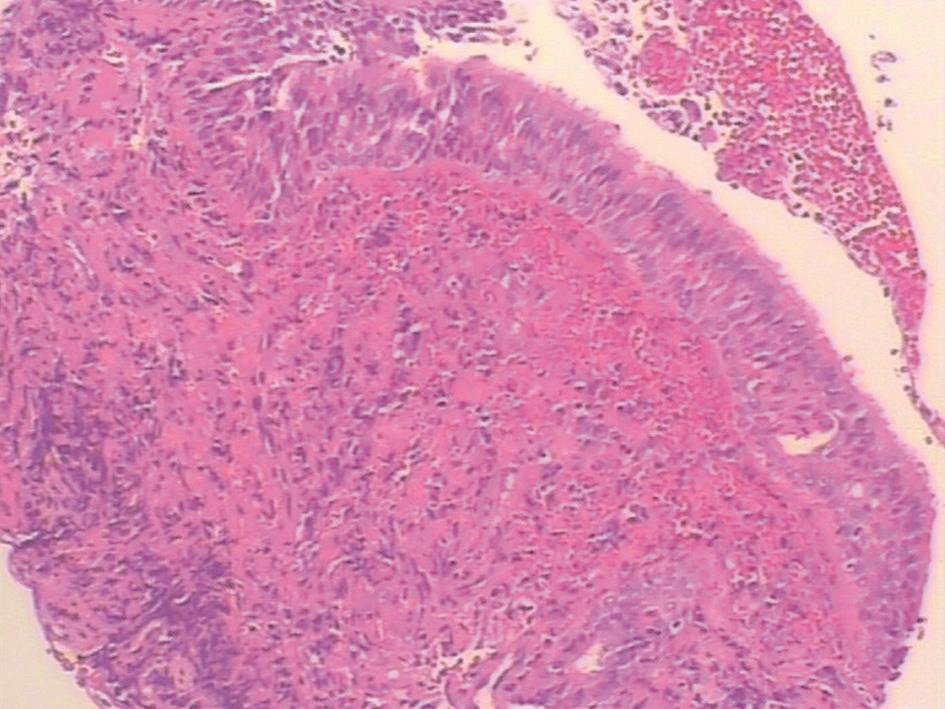

电子支气管镜检查(2016年2月2日):

支气管镜下见气管黏膜糜烂(图2)。右中间支气管黏膜活检病理示支气管黏膜慢性炎症,鳞状上皮增生,黏膜糜烂坏死,肉芽组织增生,间质大量急慢性炎症细胞浸润,并见多核巨细胞反应(图3),刚果红染色阳性,抗酸染色阴性。

图2 支气管镜下见黏膜糜烂

图3 右中间支气管黏膜活检病理(HE染色,×100)